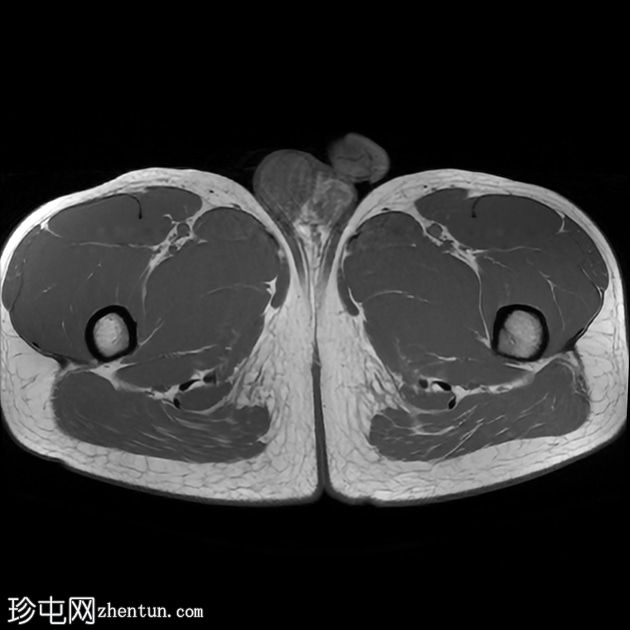

轴位

T2加权像

前列腺大小为32.8 x 41.5 x 34.7 mm(前后径 x 宽度 x 头尾径),体积为25.88 ml,属于正常范围。前列腺中央可见一逗号状囊性占位性病变,大小为17.3 x 12.1 x 9.3 mm(头尾径 x 前后径 x 宽度)。可见囊肿与前列腺尿道相通。囊内未见可疑内容物——具体而言,未见囊内出血或碎屑——弥散加权成像结果为阴性,提示无囊内感染。

动态增强扫描显示前列腺呈均匀强化,未见可疑的周边部或移行区异常。精囊正常。膀胱正常。盆腔内未见可疑淋巴结。

本例为一例发生于青年人的单纯性逗号状中央型前列腺内囊肿。

根据囊肿位于前列腺中央或中线(精阜水平)、患者年龄(二十岁左右)以及无前列腺外延伸和明显的尿道交通,前列腺囊肿是首选诊断。苗勒氏管囊肿通常难以排除。患者的年龄、无前列腺外延伸以及疑似尿道交通使该诊断的可能性降低。